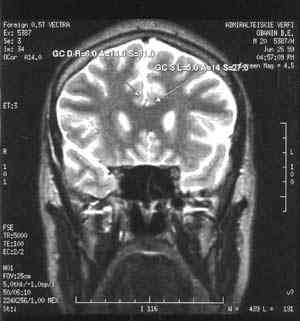

Именно наличие клиники во многом определяет возможности фундаментальных и прикладных исследований ИМЧ. Поэтому прежде всего несколько слов о ней. У нас прекрасные высококвалифицированные доктора и медсестры. Без этого нельзя: ведь мы на переднем крае, и нужна высочайшая квалификация, чтобы выполнять нерутинное, новое. У нас выполняются практически все стандартные манипуляции и наряду с ними и хирургическое лечение эпилепсии и паркинсонизма, проводятся психохирургические операции, в том числе и хирургическое лечение обусловленного героином обсессивно-компульсивного синдрома, знаменитая «пересадка мозга», точнее имплантация фетальной мозговой ткани, лечение магнитости-муляцией мозга, лечение афазии с помощью электростимуляции и многое другое. Накоплен десятилетний опыт клинических обследований с помощью позитронно-эмиссионной томографии. На рисунках приведена малая толика того, что может диагносцировать этот метод томографии. У нас лежат тяжелые больные, и мы стараемся помочь с помощью вышеперечисленных методов даже тогда, когда все остальные попытки были неудачны. Конечно, это удается не всегда. Но безграничных гарантий в лечении людей дать невозможно, а если кто-то дает их, это всегда вызывает очень серьезные сомнения.

Рассеянный склероз - тяжелое хроническое заболевание головного и спинного мозга, поражающее сравнительно молодых людей 20 - 40 лет. Неясность многих вопросов возникновения и механизмов развития заболевания, трудности диагностики на ранних стадиях развития, разнообразие клинических вариантов течения с быстрой инвалидизацией, отсутствие эффективных методов лечения вывели изучение рассеянного склероза в круг наиболее актуальных задач современной медицины. В лаборатории нейроиммунологии Института мозга человека РАН разработан новый подход, позволяющий одновременно с использованием специфичных иммунологических методов оценки поражения клеток центральной нервной системы применять магнитно-резонансную и позитронно-эмиссионную томографию для визуализации патологического процесса. Принципиальная новизна состоит в том, что данный подход позволяет одновременно оценивать как системные аутоиммунные нарушения при рассеянном склерозе, так и локальные функциональные и морфологические изменения в центральной нервной системе. Комплексное нейроиммунологическое, инструментальное, клиническое обследование пациентов с рассеянным склерозом позволило установить важную роль поражений коры и подкорковых структур в механизмах развития этого заболевания.

Современная нейрохирургия использует проверенные временем методики точной локализации поражения в мозге и сегодня это, в первую очередь, осуществляется методами магниторезонансной томографии, разрешение которой перекрывает потребности для определения места хирургического вмешательства. В типичных условиях современной клиники